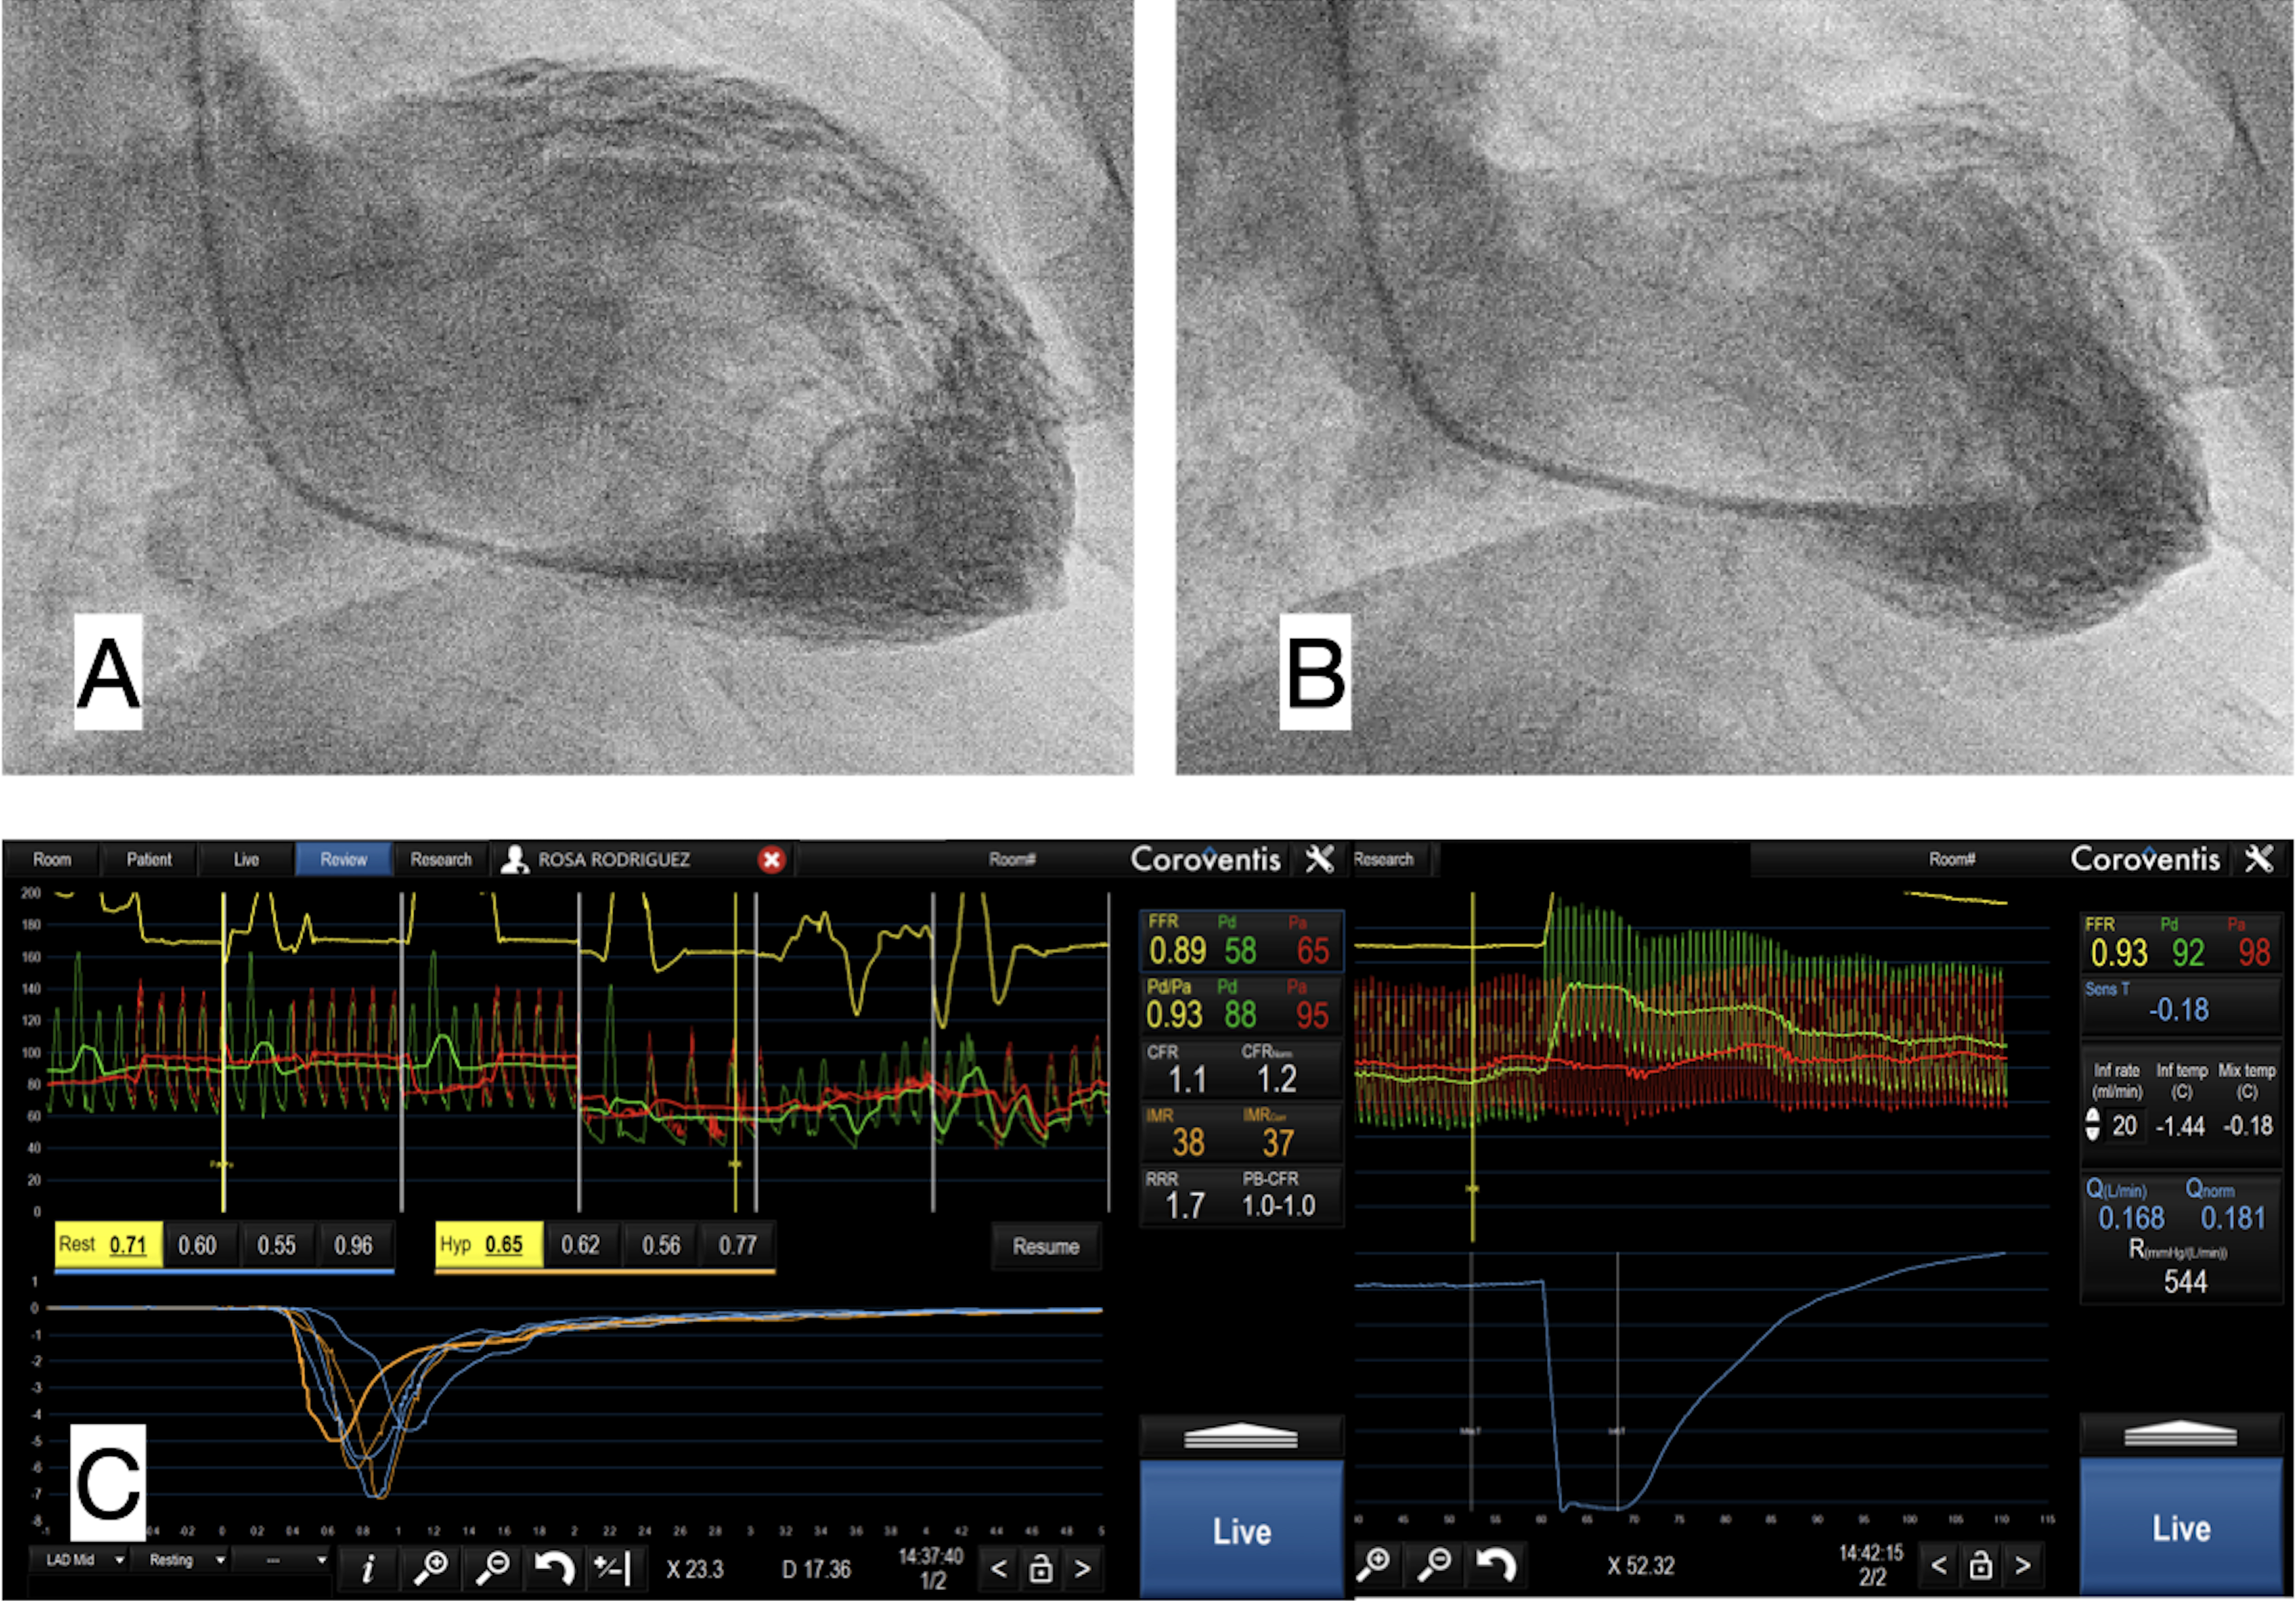

Fig. 1.Ventriculography and coronary physiology in Takotsubo Syndrome. (A) Ventriculography in telediastole. (B) Ventriculography in telesystole, with apical akinesia or apical ballooning. (C) Coronary invasive physiology in Left Anterior Descending coronary artery with Fractional Flow Reserve (FFR) 0.89, Coronary Flow Reserve (CFR) 1.1, Index of Microcirculatory Resistance (IMR) 38, meaning low coronary flow with high microvascular resistances without epicardial coronary lesions.

The coronary flow and coronary microcirculation parameters usually analyzed include (Fig. 1C):

- Coronary Fractional Flow Reserve (FFR), considered the ratio between mean pressure distal to the stenosis (Pd) and mean aortic pressure (Pa), values below 0.8 mean a significant coronary lesion.

- Coronary Flow Reserve (CFR), considered as the ratio between coronary flow at maximal hyperemia and at baseline conditions. Normal value is above 2.

FFR and IMR in TTS have been evaluated, showing normal FFR but significant CMD associated with high IMR values. On the other hand, a significant drop has been described in HMR values in response to adenosine, that could help to identify the TTS cases most likely to benefit from coronary vasodilator strategies, thus improving overall prognosis for the patients [17].